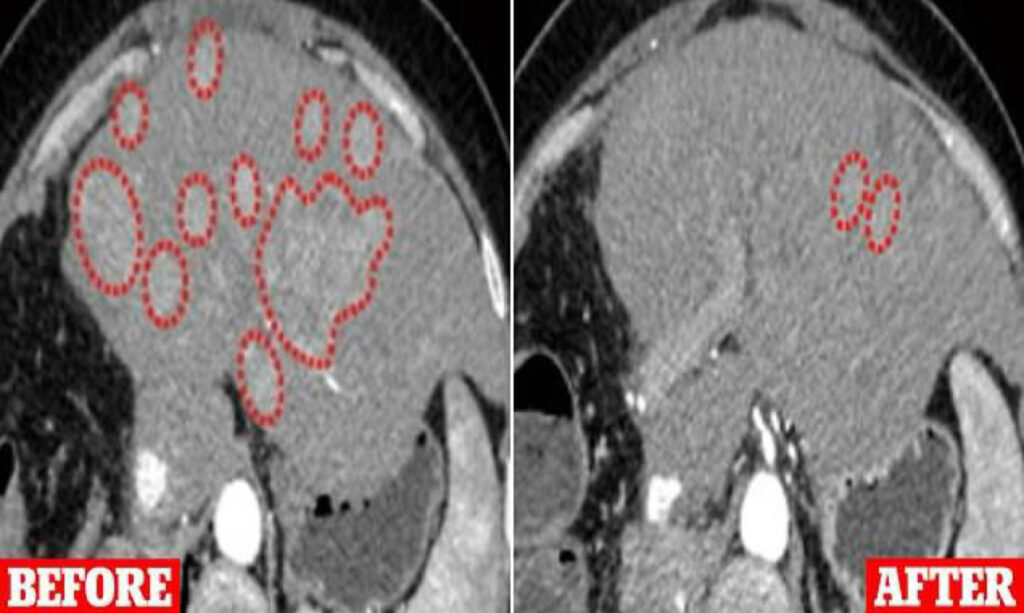

This experimental therapy, involving a modified avian virus, was tested on 23 patients with diverse cancers, including breast, lung, and skin cancers, who had previously not responded to standard treatments. Remarkably, all but one patient experienced tumor shrinkage or halted tumor growth after receiving weekly infusions for 8 to 12 weeks. Additionally, trials on monkeys with liver cancer demonstrated increased survival rates compared to those receiving a placebo.

Initial trials on monkeys with liver cancer showed significant survival benefits for those receiving the therapy. The human trials involved patients with advanced cancers who typically have limited survival prognoses.